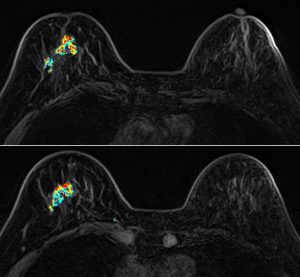

三、乳房MRI磁振造影檢查

無輻射、高解析度、無痛的高階影像檢查,對偵測腫塊病灶有極高的靈敏度,是極佳的診斷利器。

適用對象:有乳癌家族史、曾罹患卵巢癌及子宮內膜癌者、帶有特定家族遺傳基因(BRCA1、BRCA2等)等高危險族群,以及曾接受乳房手術的女性(如自體脂肪豐胸、假體植入),建議至少每2年做一次MRI檢測,除偵測早期乳癌外,同時可評估植入物之完整性。

【個案分享】

64歲石小姐,曾接受矽膠注射隆乳(小針美容),因右側乳房疼痛而求診,但因矽膠隆乳者在乳房攝影(圖A)及超音波下會遮蔽病灶而無法診斷,因此進一步安排磁振造影MRI(圖B)發現:右側乳房有一不規則狀的腫塊(約55mm),併有右側乳頭內縮,高度懷疑惡性腫瘤,經手術證實為乳癌。

(A)

(B)